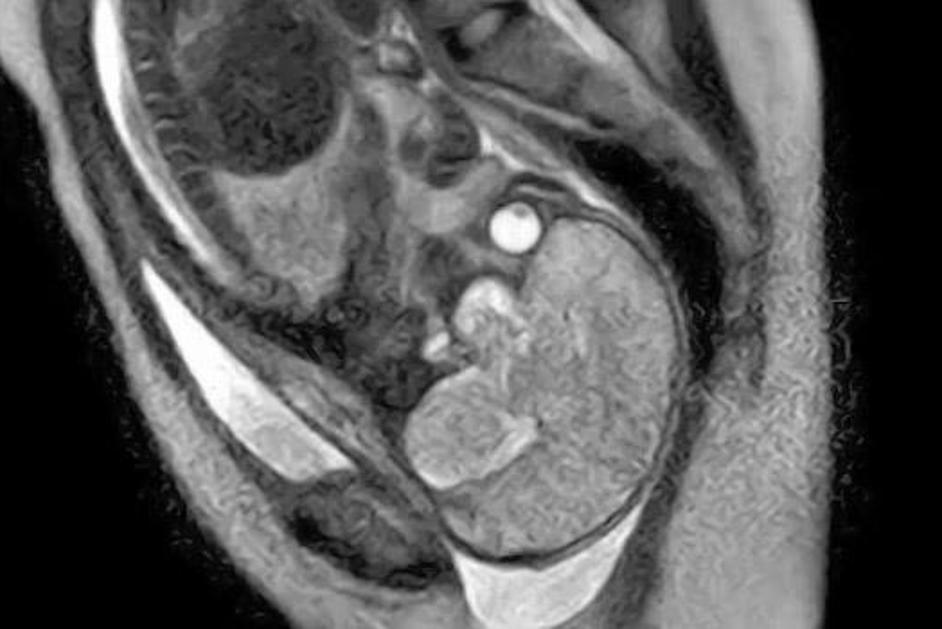

porod, snemanje, magnetna resonanca Poporodni pogled v notranjost maternice s placento. Žurnal24 porod, snemanje, magnetna resonanca